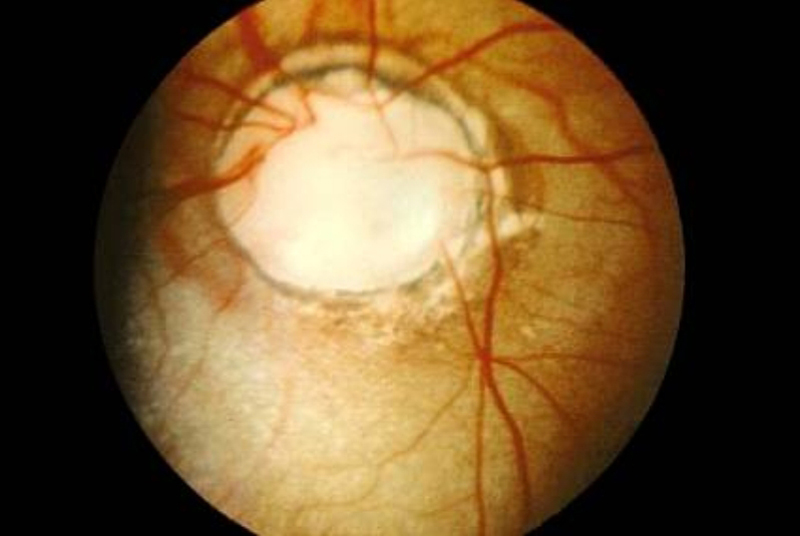

- Oclusión de vena central de la retina

El diagnóstico es clínico, aunque existen casos atípicos asociados a procesos retrobulbares infiltrativos que deben ser estudiados con RM de cráneo y órbita:

- Paciente joven sin factores de riesgo cardiovascular.

- Signos de oclusión arterial asociados (típico de gliomas malignos, aunque no exclusivo).

- Signos orbitarios (proptosis, congestión, oftalmoplejía).